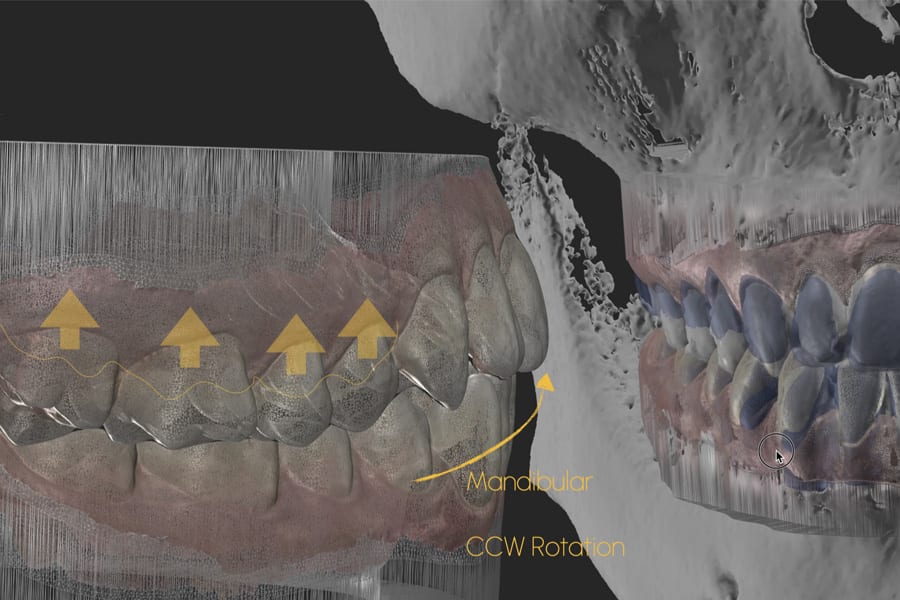

Key determinants in dentofacial analysis include tooth display at rest and during smiling, smile arc consonance, gingival display (ie, gummy smile), and symmetry of the buccal corridors. In patients with high tooth and gingival display, anterior intrusion may further accentuate esthetic disharmony. Therefore, treatment planning frequently favors posterior intrusion combined with CCW mandibular autorotation while preserving the anterior vertical dimension—that is, maintaining the vertical position of the maxillary and mandibular incisors relative to the lips and facial reference planes—to protect smile esthetics and facial harmony.4-8

Airway/dentofacial: Preserve the anterior vertical; plan posterior intrusion to reduce display via mandibular CCW autorotation. (Figure 5 and Figure 6)

Functional Planning: Counterclockwise Autorotation and Anterior Clearance

Posterior intrusion (eg, approximately 2 mm to 3 mm molar intrusion) is modeled to define mandibular CCW autorotation, ensuring acceptable anterior guidance and envelope. Hybrid analog/digital or fully digital jaw-tracking/axiography improves precision for the terminal mandibular position at treatment completion.9-11 (Figure 10 through Figure 13)